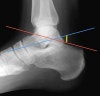

Boehler’s angle

<25º is a fracture with displacement through the calcaneus.

Red line : From posterosuperior calcaneal tuberosity to tip of the posterior facet of the subtalar joint

Blue line : From tip of posterior facet through superior margin of anterior process of calcaneus